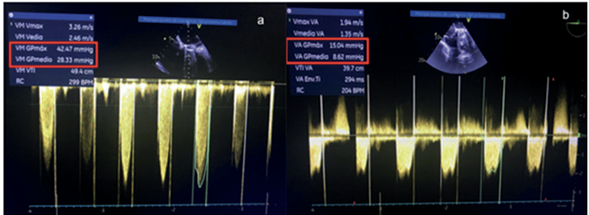

El ecocardiograma transesofágico con compresión extrínseca de la FAV reveló un inmediato descenso significativo del gradiente transmitral (Figura 3) y desaparición de la IT.

Figura 3 Ecocardiograma transesofágico donde se evidencia caída del gradiente máximo (VM GP máx.) y del gradiente medio (VM GP medio) transvalvular mitral pre (imagen a) y post (imagen b) compresión extrínseca de FAV HC.

El CCD basal mostró Hipertensión pulmonar postcapilar aislada y gasto cardiaco (GC) elevado. Presión arterial pulmonar media (PAPm) de 49 mmHg, Presión de oclusión de arteria pulmonar (POAP) de 28 mmHg y Resistencia vascular pulmonar (RVP) de 2,5 U. Wood. Bajo compresión extrínseca de la FAV-HC, se evidenció una reducción significativa del gradiente medio transvalvular mitral (de 23 a 9 mmHg), reducción del GC (de 8100 a 5700 ml/min) y de la PAPm de 49 a 38 mmHg (Tablas 1,2 y 3).